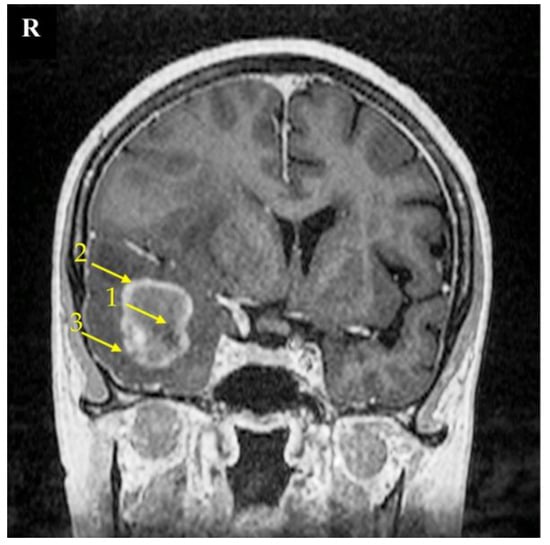

The research material consisted of samples taken from three areas of the tumor: the non-enhancing tumor core (usually located in the central part of the tumor), the enhancing tumor region (surrounding the tumor core), and the peritumoral area (a buffer zone between the tumor and healthy tissue, with individual foci of infiltration) (Figure 9) [54,55]. We considered the peritumoral area as the experimental control; as previously shown, this is suitable control for GBM-related experiments [56]. The identification of individual parts of the tumor was based on the neuronavigation method during surgery.

Figure 9.

Magnetic resonance imaging (MRI) scan of a brain with the right temporal lobe GBM tumor. This 67-year-old female had reported a two-week-long headache and was administered due to a seizure. MRI imaging shows a non-enhancing tumor core (1), enhancing tumor region (2), and peritumoral area (3). The signs of brain structure shift due to tumor growth expansion are seen as well. The right side of the patient was marked with the letter R.

A neuronavigation-guided biopsy recovered the glioblastoma structure in the sample tissue, so it was then followed by a craniotomy and tumor resection. The patient was discharged 9 days post operation with a recommendation of radiotherapy and chemotherapy.